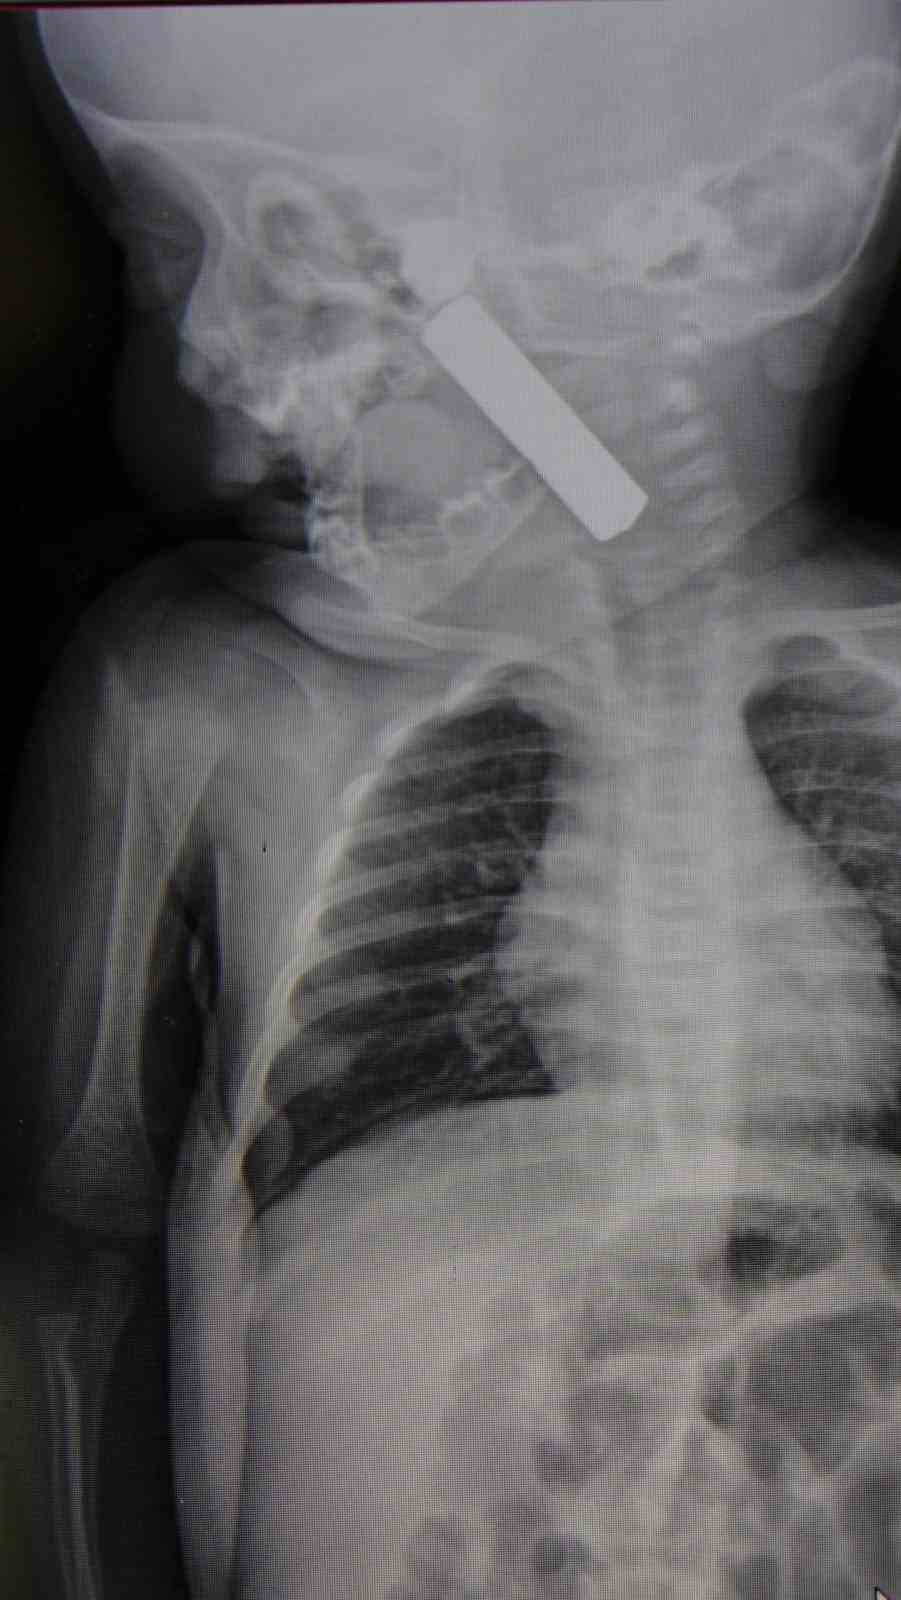

Edinilen bilgiye göre, kusma şikayeti ile ailesi tarafından Karaman Eğitim ve Araştırma Hastanesi acil servisine getirilen 6 aylık E.A. isimli kız bebeğin, yapılan muayene ve tetkiklerde boğazında kumanda pili kaçtığı tespit edildi. Solunum sıkıntısı da yaşayan bebek hemen ameliyata alındı. Çocuk Cerrahisi Uzmanı Doç. Dr. Mehmet Uysal tarafından yapılan ameliyatla bebeğin boğazındaki pil çıkarıldı.

Yaşanan olayla ilgili bilgi veren Doç. Dr. Mehmet Uysal, "Acil polikliniğimize kusma şikayeti ile 6 aylık bir kız bebek getirilmiş ve bize haber verildi. Biz de vakit kaybetmeden geldik, hastamızı gördük. Yapılan tetkikler sonucunda, ağız tabanına oturan ve yemek borusunun birinci darlığına kadar uzanan, kumanda pili dediğimiz bir pille karşılaştık. Filmde ve muayenede bunu gördük. Hastayı ilk gördüğümüzde bayağı siyanotik durumda, solunum sıkıntılıydı ve oksijen satürasyonu 90 civarındaydı. Böyle olunca bir an önce beklemeden hızlı bir şekilde ameliyathaneye götürdük. Orada ameliyathanedeki anestezi uzmanlarımız ve personel bize yardımcı oldu, hasta hızlı bir şekilde entübe edildi. Ondan sonra da laringoskop ve magill forseps dediğimiz malzemelerimizle bu yabancı cismi çıkarmış olduk. Bir an evvel müdahale ettik, iyi ki müdahale ettik, orada ağız tabanında, özellikle ön kısmında hasar oluşmuştu. Müdahale sonrasında da hastanın solunum problemleri bir süre devam etti, bu yüzden 24 saat takip ettik. Herhangi bir problem oluşmayınca 24 saat sonra kontrole gelmek üzere hastayı taburcu ettik" diye konuştu.